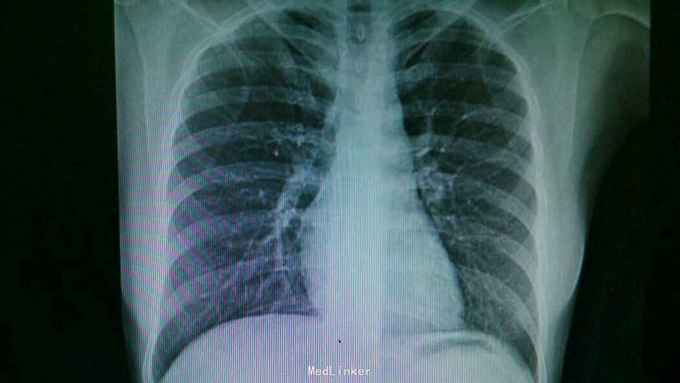

查体:双肺呼吸音粗,右肺可闻及湿罗音, 余无特殊 辅查:血常规示中性粒细胞稍高。胸片:右上肺野炎性病变。肺炎支原体抗体滴度1:640。胸部CT:双肺炎症。

诊断:支原体肺炎。 治疗,予以阿奇霉素抗感染,止咳化痰等处理。复查胸片提示炎症较前好转。